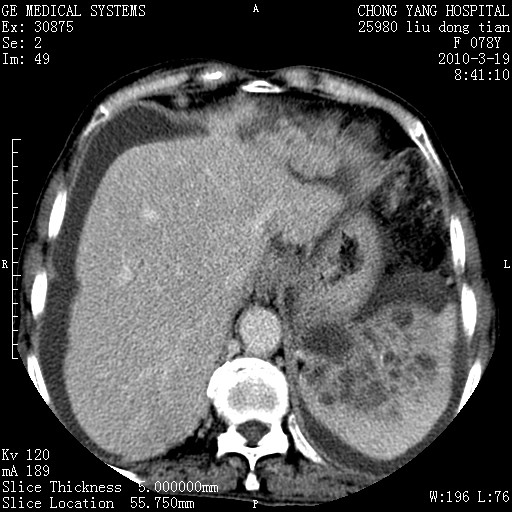

标题: CT25199:F 78Y 腹胀半年 消瘦乏力 [打印本页]

胆囊壁增厚并明显强化,胆囊癌伴多发转移瘤可能性大,淋巴瘤不除外,右肾囊肿,胸腹水.

考虑nhl,肝、脾、腹膜腔及腹膜后多发淋巴结受侵,腹水,右肾囊肿,慢性胆囊炎,右侧少量胸腔积液。

胰头有肿块形成,胰头ca伴肝脾、腹膜腹膜后转移

胆囊有软组织影有强化,支持胆囊癌,肝脾、腹膜后淋巴结转移。

nhl的淋巴结多围绕主动脉,而且主动脉会移位,所以不考虑nhl。

分开来讲:肝左叶、尾叶病灶有不均强化像肝癌;

脾脏病灶无强化,像多发囊肿或淋巴管瘤,不除外淋巴瘤(低强化);

肝门、胰腺头、腹膜后多个团块: 淋巴瘤,转移;

一元论最好了 淋巴瘤所致改变; 胆囊癌转移不像,胆囊周围肝组织清晰,肝癌淋巴结转移?三元论都不止。

最后报的胰头癌多发转移,脾脏单独考虑囊肿或淋巴管瘤。